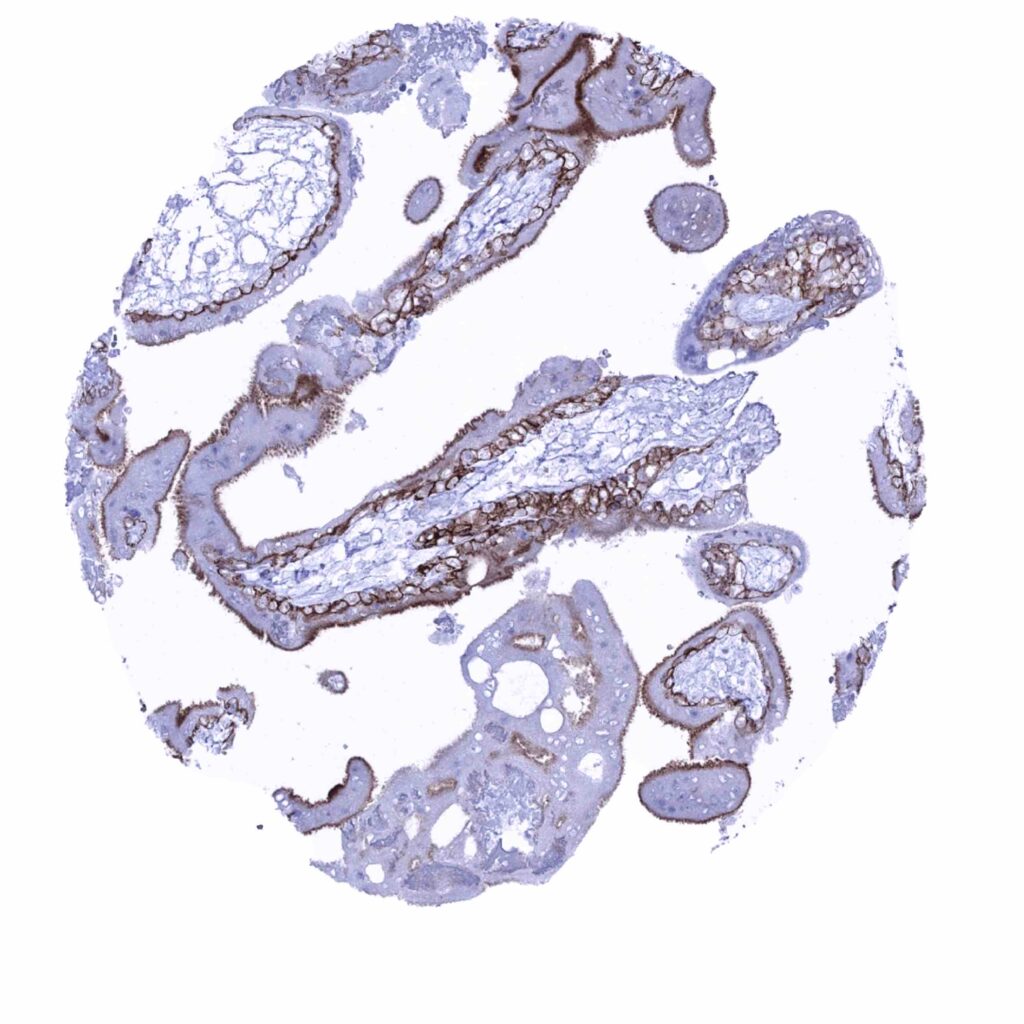

Fallopian tube, mucosa – Membranous occludin positivity is diffuse but strongest at the apical membrane (occludin immunohistochemistry)